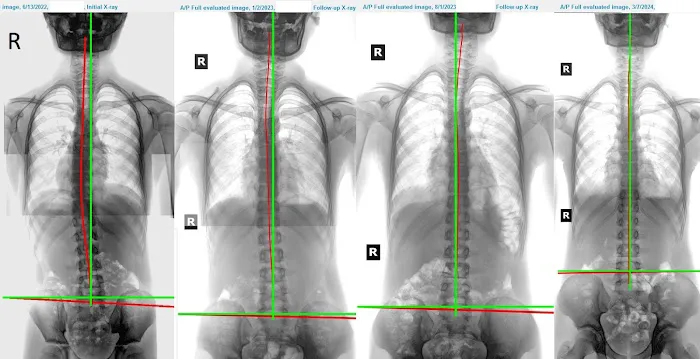

On-site X-rays: The ability to take and analyze X-rays in the office for a thorough understanding of spinal health, alignment, and degeneration.

Tangible Health Improvements: Beyond pain relief, patients report their "spine is getting younger and healthier" over time, showcasing the long-term, positive impact of consistent care.

Dec 05, 2024 · Rachael K.This is not your typical Chiropractor's office where you get a 10 minute spinal adjustment or receive automated spinal decompression. Rather, Dr. Park uses mechanical traction equipment to remodel the deformed or injured spine following computerized spinal analysis based on photographic and radiologic input. I was referred to Dr. Park from my personal trainer because of age related postural deformity. In just 2 months the results have been significant and I have actually started to regain lost height in addition to markedly improved posture. Moreover, my low back, hip and shoulder pain has resolved almost completely.